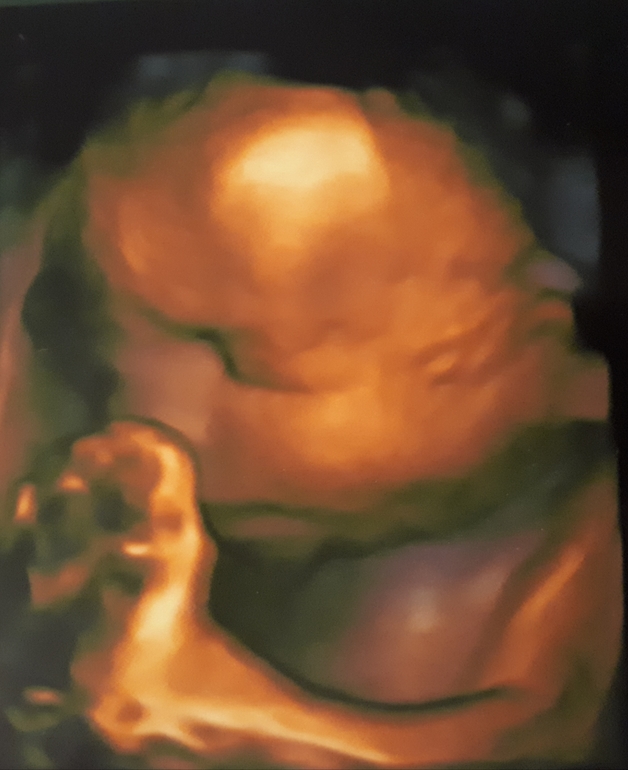

Кончается 33яя неделя нашей долгожданной беременности. Общая прибавка уже почти 8кг, а кушать еще недель 7 (интересно мы хотя бы в 10тку уложимся🤣). Фото животика ниже и фото с последнего 3Д узи, где мы закрывали лицо руками и ногами)))